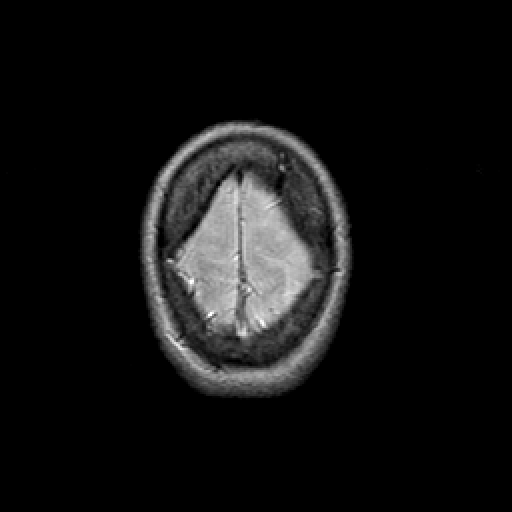

Proton density-weighted structural MR: Slice 48

Slice 48